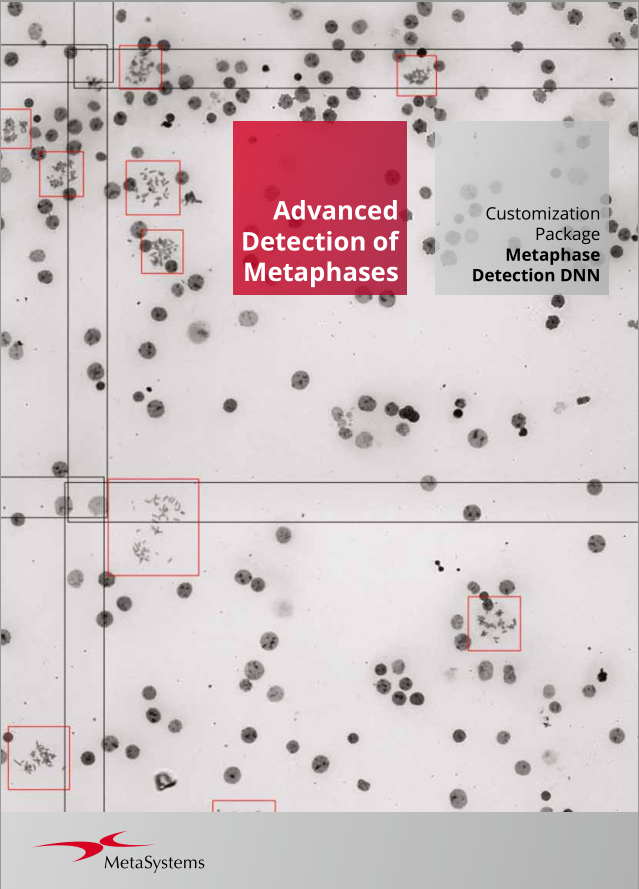

Metafer’s classifier system brings smart automation to object recognition. Combining advanced algorithms with user-defined criteria, it lets users categorize samples quickly while keeping workflows consistent and reliable. With integrated Deep Neural Networks (DNN), Metafer handles diverse sample types with precision, flexibility, and intelligence.

MetaSystems software provides, among other functions, features to assist users with image processing. These include, but are not limited to, the use of machine and deep learning algorithms for pattern recognition. The output generated in this process should be regarded as preliminary suggestions and, in any case, mandatorily requires review and assessment by trained experts.